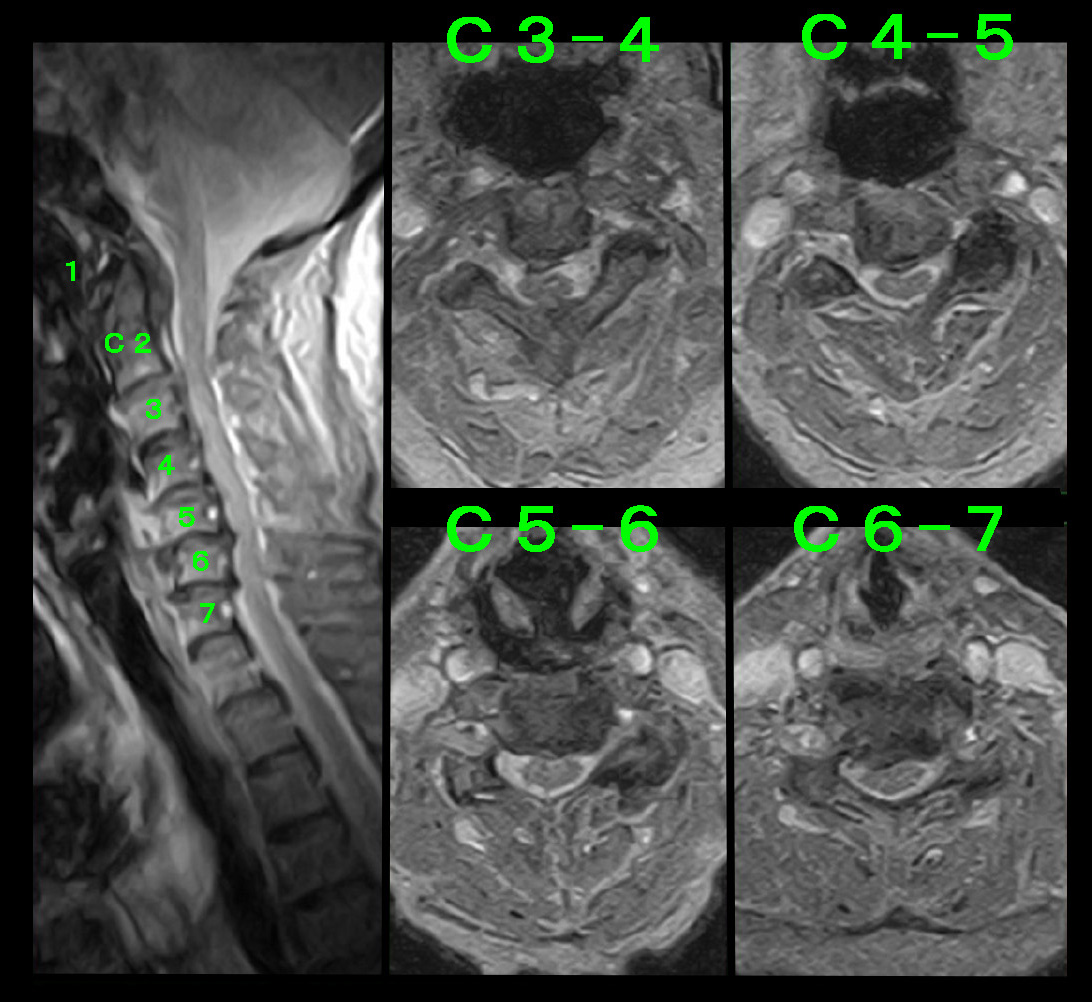

それから2か月後の令和1年6月10日に右手のしびれで物を触っている感覚がないということで受診されています。この時はチネル兆候もファレンtestも陽性で、手根管症候群の手術も視野に入れて両手関節のMRI検査を行っています。

手根管MR1.jpg

手根管MR2.jpg

手関節を水平に切った画像です。中央部のスイカの種のような部分が手指の屈筋腱ですが、ピンクで囲った領域が正中神経の位置するところとなります。2つの断面とも右手関節で正中神経は重度に圧迫されていることが分かります。

この時も手根管注射をしたのですが、全く効果がなかったということで症状の改善には手術しか有効な治療法はなくなりました。当然、手術を勧めたのですが、患者さんは不自由じゃないから大丈夫という見解となりました。